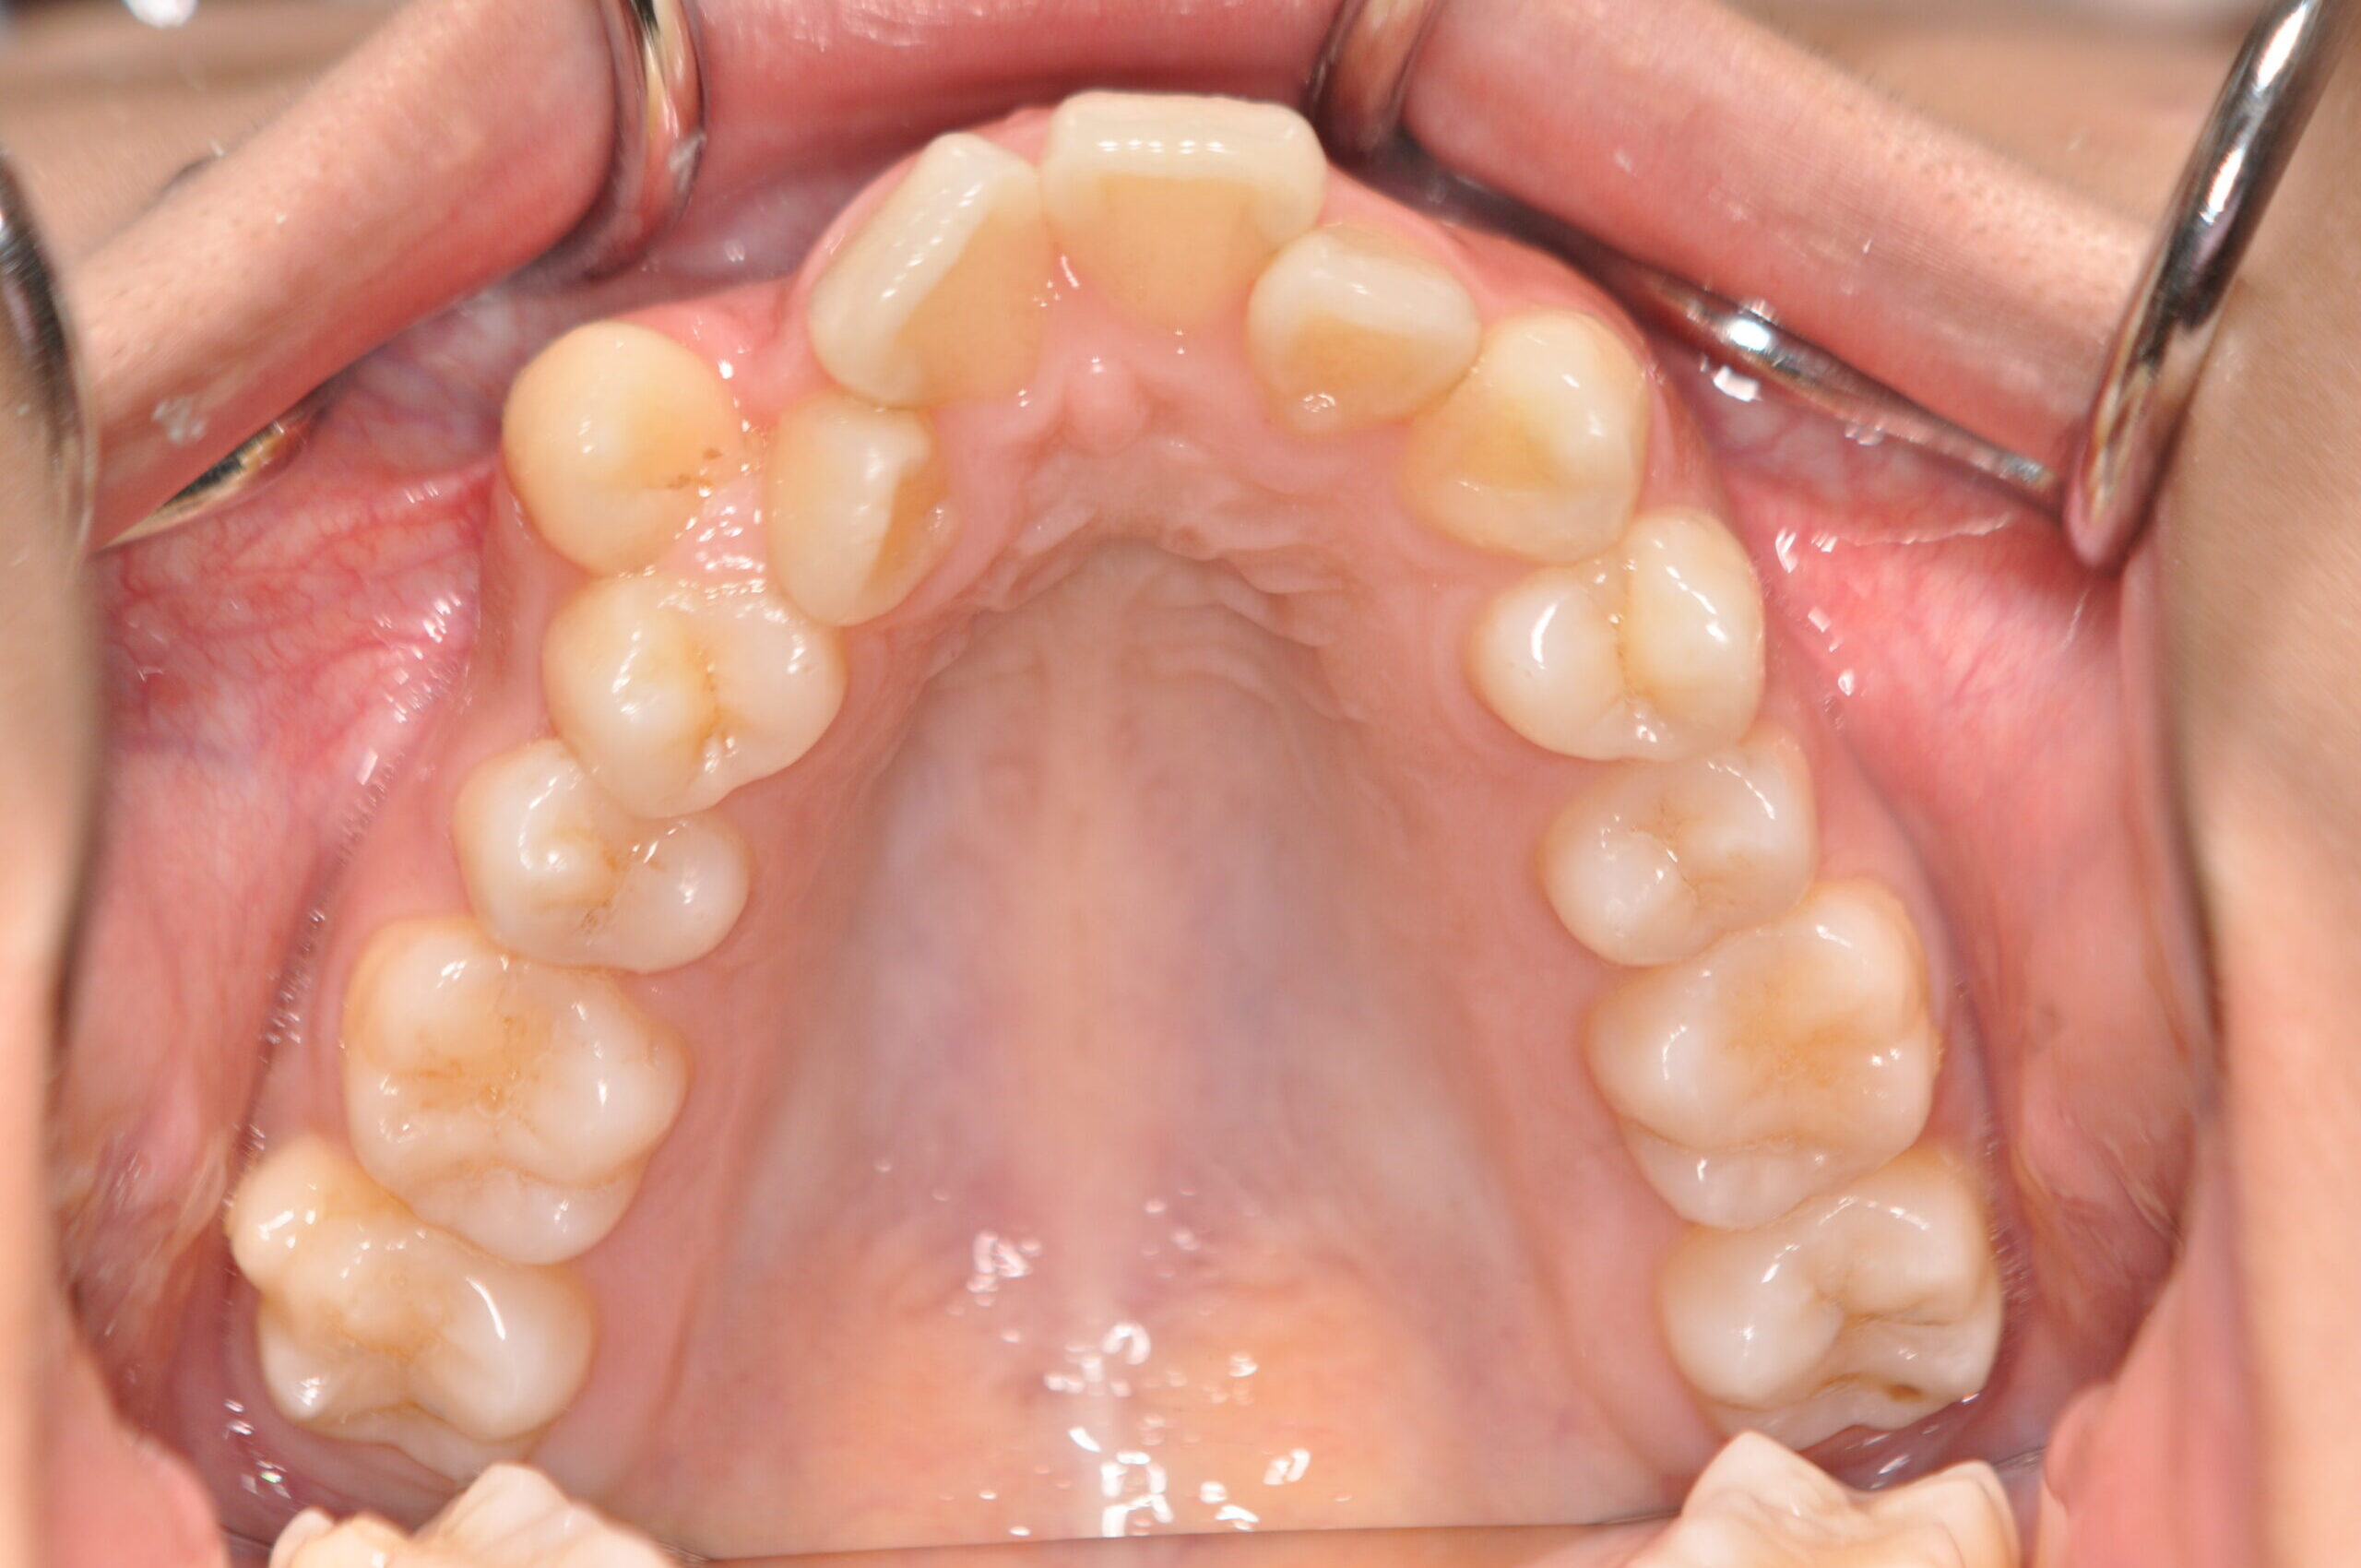

初診時

症例 症例 症例 症例

年齢

20歳5ヶ月 性 別 女性

検査の結果、上顎前突及び上下顎前歯部叢生を伴うアングルⅡ級1類不正咬合と診断しました。